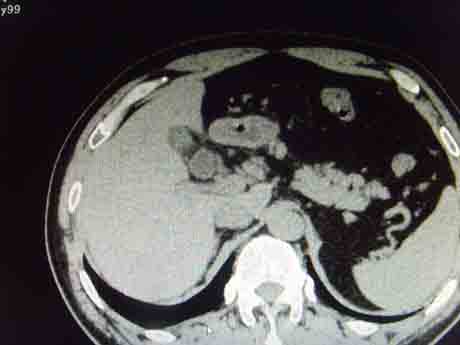

CT50893:胆囊积气诊断什么?

本帖最后由 cefcmj 于 2015-7-22 18:28 编辑 男,44岁,右上腹剧痛,胆囊积气诊断什么?

胆囊密度不均,内见气体密度影,胆囊壁稍厚,考虑气肿性胆囊炎,化脓性胆囊炎?

气肿性胆囊炎。支持。

气肿型胆囊炎

产气菌感染所致气肿性胆囊炎。相同情况亦可见气肿性肾盂肾炎、膀胱炎。

胆囊类固醇结石并胆囊炎

类固醇结石